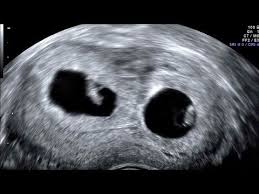

By four weeks twins will start showing during ultrasound in form of 2 gestational sacs but you cannot get clear indication of twins until 6 weeks. An ultrasound with twins will show the babies as two dark spots in the uterus. If your health care provider can only see one baby it is not likely that you re having twins or multiples. Your baby will become visible on ultrasound when they are only 2 3mm long but you will have to wait to see more details.

Your babies will be developing rapidly but a 6 week ultrasound for twins provides you with more details about your multiples. Measuring ahead isn t an early sign of twins as it s unlikely that your provider will measure your belly until after 20 weeks of pregnancy. At this stage the presence of two yolk sacs can be seen and separate heartbeats distinguished. Typically the end of your first trimester around 11 to 14 weeks is when you have your first ultrasound in pregnancy.